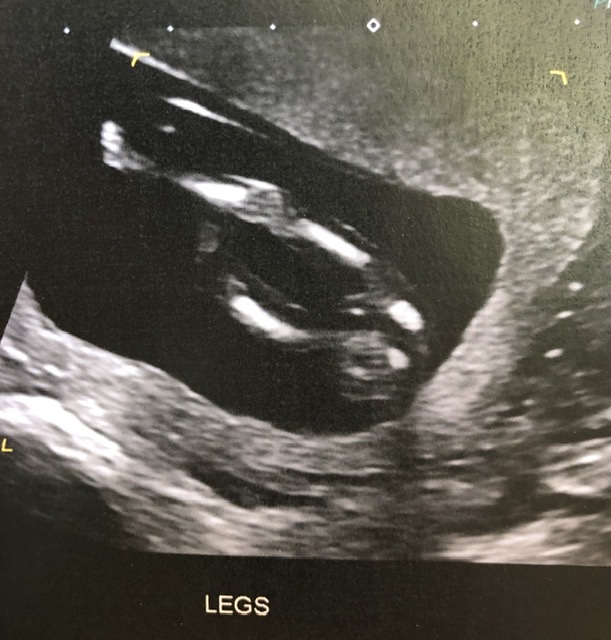

Just wondering if anyone had any guesses on these 13wk ultrasounds for fun?

I’m assuming that’s not a penis on the leg shot any maybe the cord but I can’t work out anything and I don’t think the nub is visible in the other pic Attachment 42785

Unfortunately these are not suitable for guessing. The top pic has the back of the baby's head (you can see the little ear there) and on the bottom pic,, 13 weeks is too early for potty shots. Boys and girls look the same from beneath at that stage of gestation.

No nub seen but looks similar to my 13 week scan between the legs when I had a girl so guessing girl. Take my guess with a pinch of salt though as it is a bit too early. Hope you get whatever your preference is if you have one